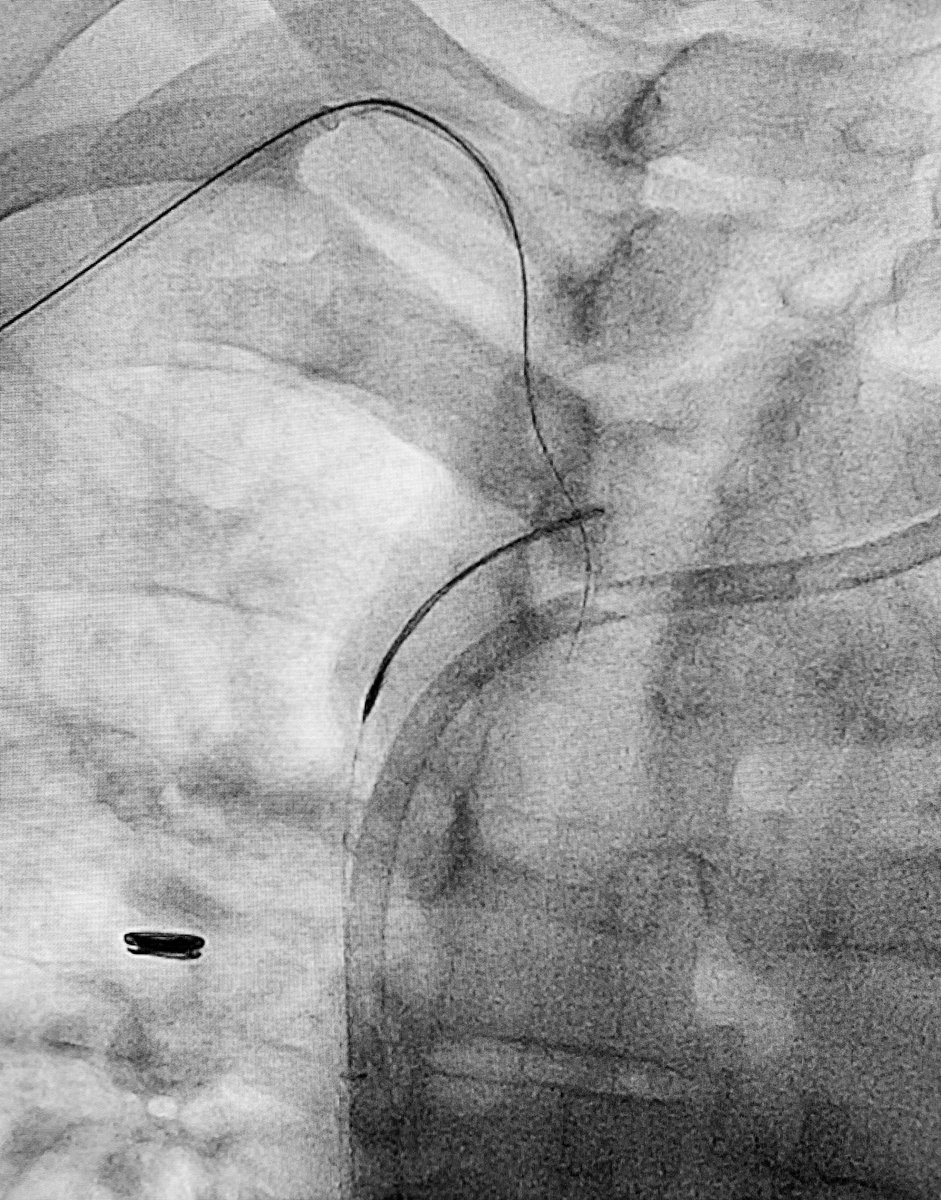

Last case of 2019. Successful

#recanalisation of chronic#splenicvein#occlusion using#transhepatic approach.#portalvein and#SMV reconstructed for#palliation#pancreaticcancer. Wish everyone happy 2020.#irad@SIRspecialists@SIR_ECS@SIRRFS@JVIRmedia@CVIR_Journalpic.twitter.com/Lgma0lTJUd